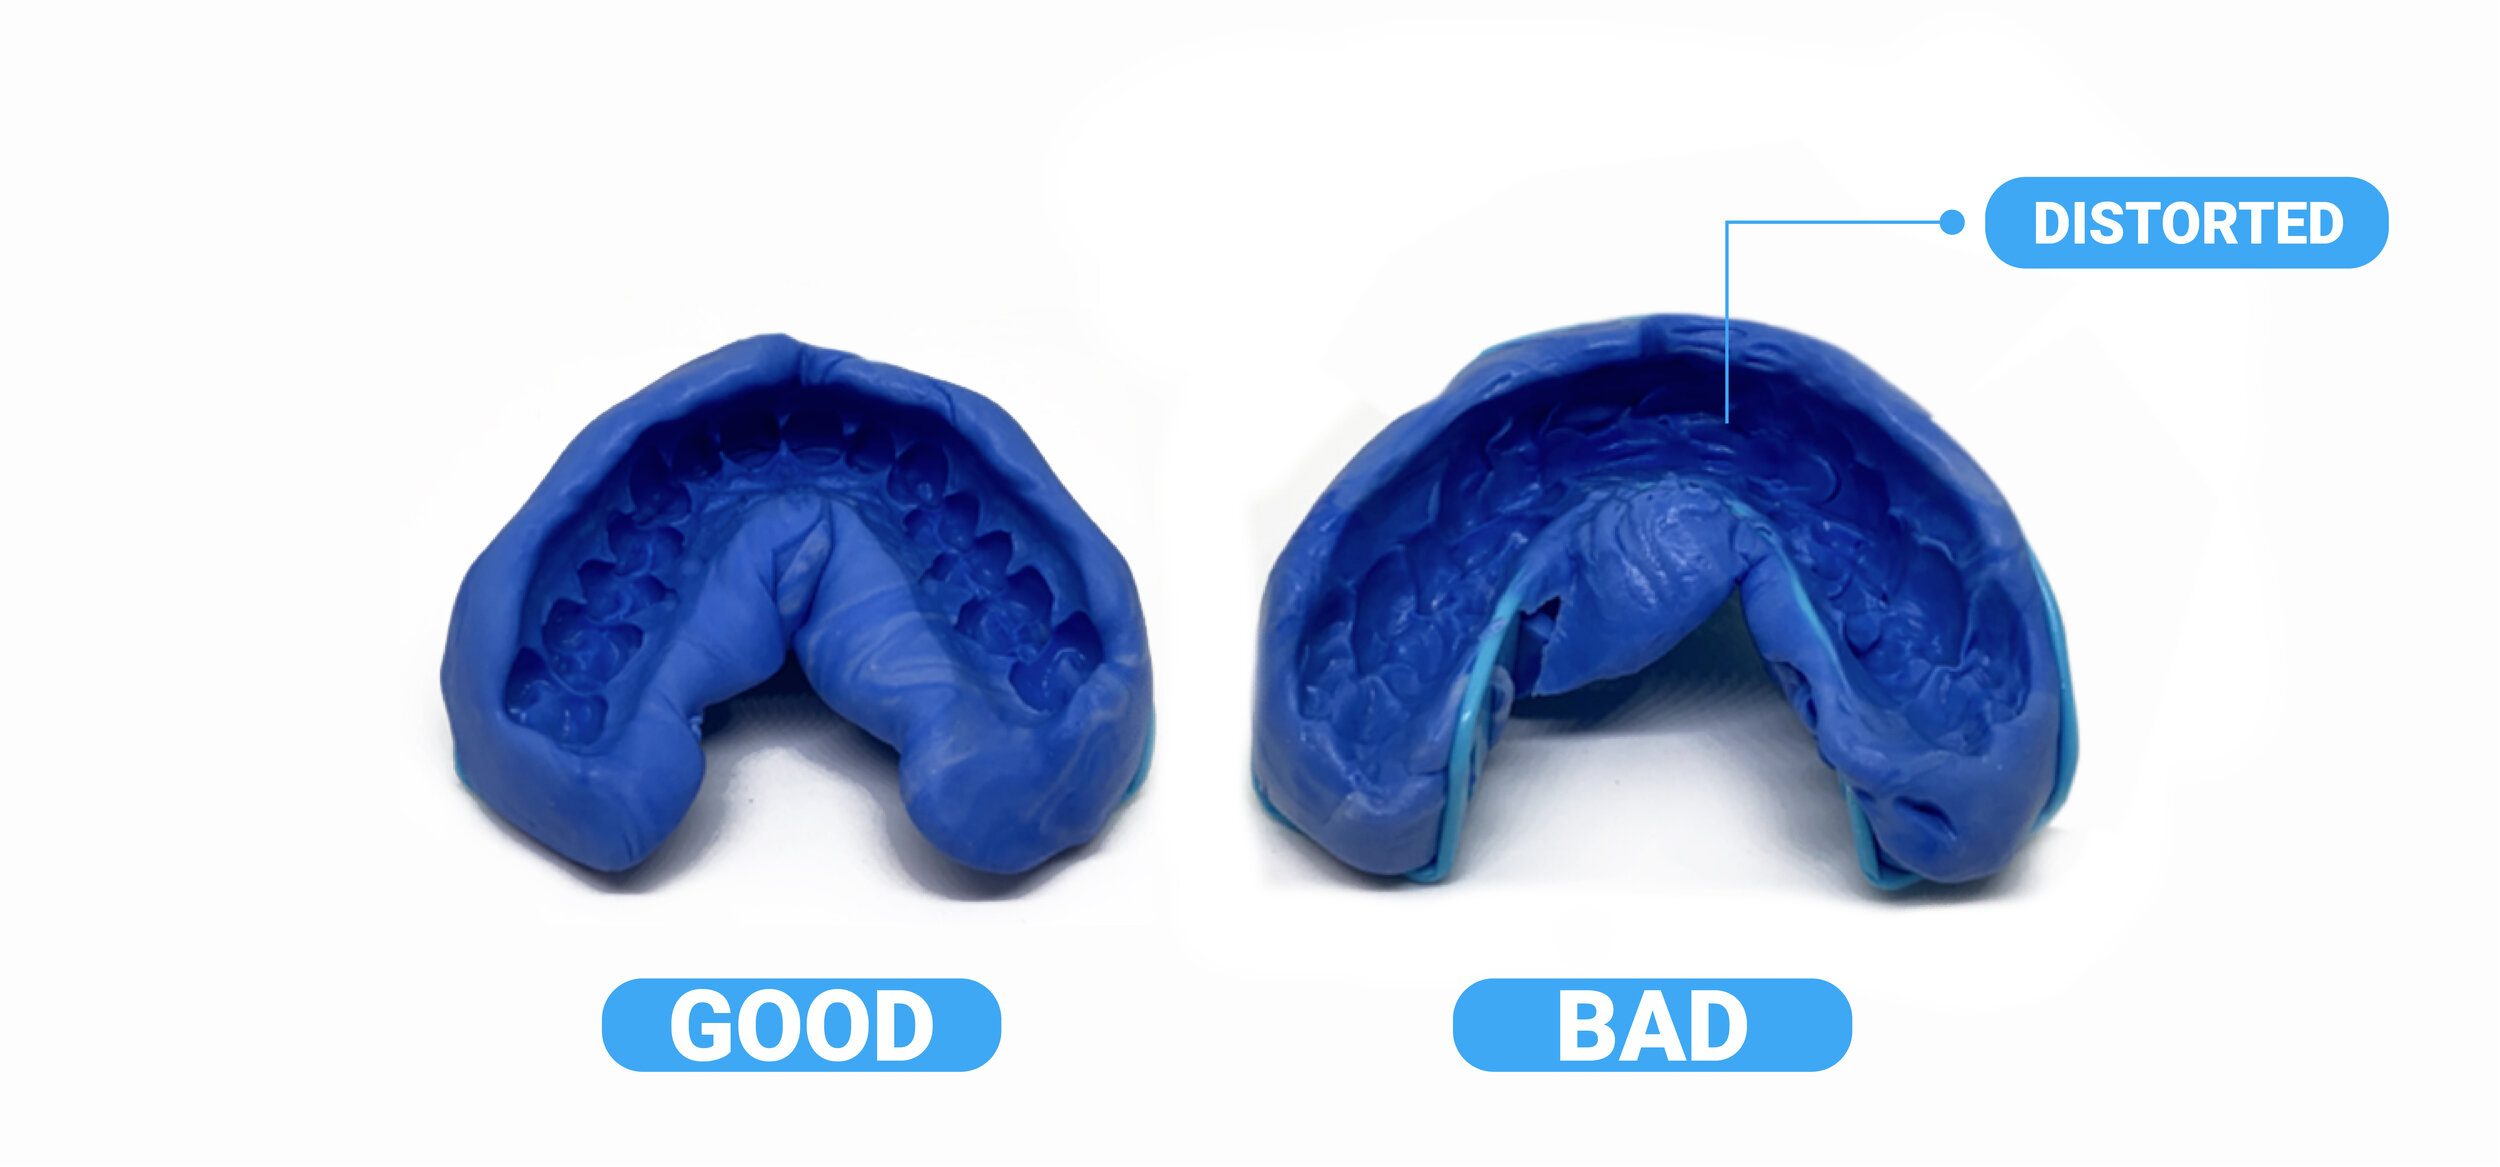

Taking Impressions

Taking Impressions

Taking Impressions

Taking Impressions

Taking Impressions

Taking Impressions

Taking Impressions

Taking Impressions

Taking Impressions

Taking Impressions

Taking Impressions

Taking Impressions

Taking Impressions

Taking Impressions

Taking Impressions

Taking Impressions

Taking Impressions

Taking Impressions

Text

Taking Impressions

Text

Taking Impressions

Taking Impressions